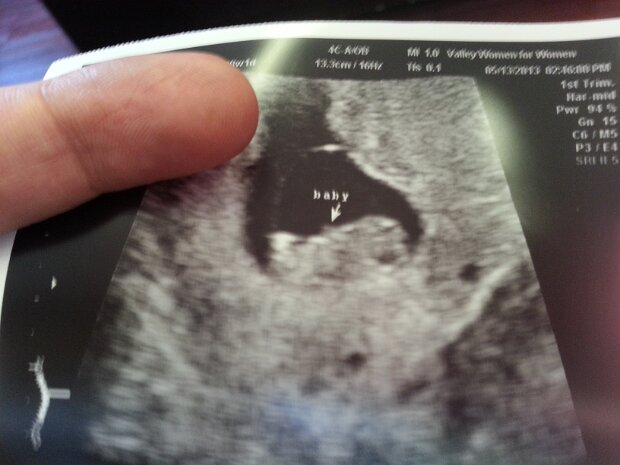

2013-05-13

5/13/13

May 13th

I'm Going To Be A Dad